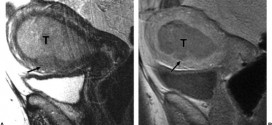

Leer MásTUMOR VESICAL QUE INVADE LA MITAD INTERNA

El tumor vesical que invade la mitad interna (T2a). Tumor maligno en general y especialmente el formado por células epiteliales, a saber. Durante los primeros años de vida de una persona, las células normales se dividen más rápidamente para permitir el crecimiento. El cuerpo está compuesto por billones de células vivas. Las células normales del cuerpo crecen, se dividen formando …